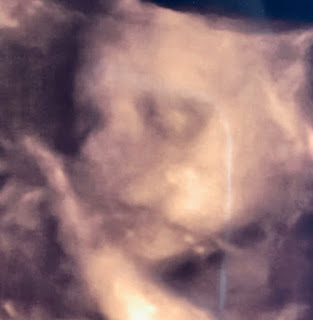

My mom and I picked Katie up at the airport on Thursday. The next day our entire family went to see Graham in a 3D ultrasound. Brad and I have seen him a lot of course but this was different. You could see his cheeks that I can't wait to kiss all over. It was neat for our parents to be a part of this experience too because they have never been to an ultrasound before. It was a day I'll never forget.